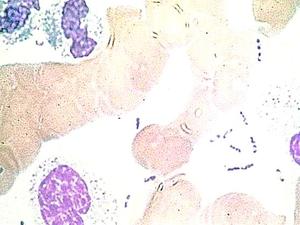

Estudio muestra primer balance positivo del uso de Sinovac en niños